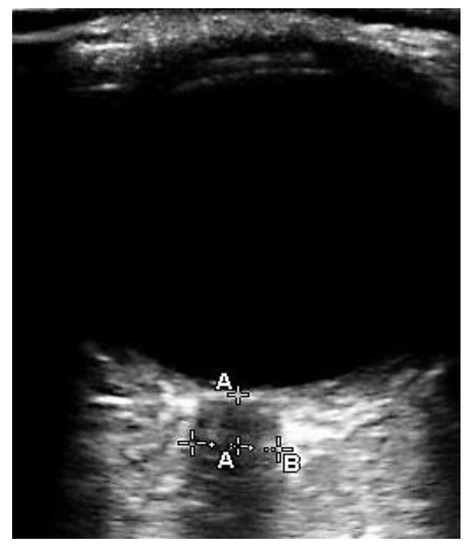

1. Introduction

2. Material and Methods

2.3. Measurements